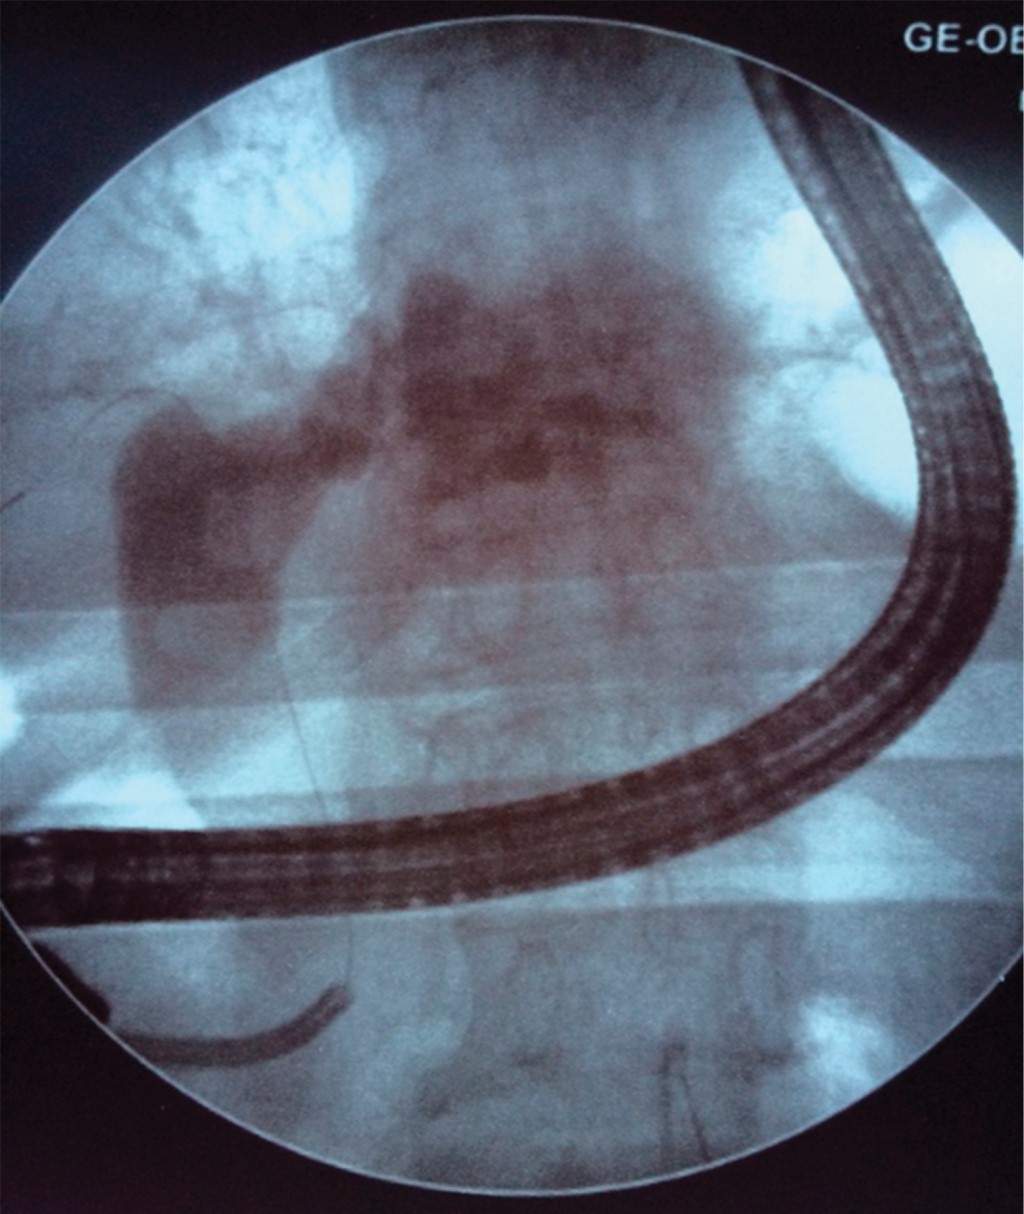

Se introdujo el endoscopio de manera proximal en la vía biliar, se aspiró la bilis y se irrigó retirando el endoscopio de manera progresiva para canular ámpula de Vater e introducir colangioscopio y observar la vía biliar en sus diferentes segmentos (Figura 1): vía biliar intrahepática, carina, hepático común, remanente del cístico y colédoco en sus tres segmentos. El procedimiento se llevó a cabo con apoyo de fluoroscopía para guiar el adecuado paso del colangioscopio hacia el conducto colédoco y conductos hepáticos (Figura 2). Los litos fueron dividiéndose secuencialmente mediante la aplicación de láser Holmio a 1.8 Joules y 10 Hertz de frecuencia en promedio hasta fragmentarlos en su totalidad o litotripsia electrohidráulica según los programas preestablecidos. Al final de la litotripsia se retiró el colangioscopio para pasar un catéter extractor de balón y hacer limpieza de los residuos de la fragmentación, dejando la vía biliar permeable y sin litos. Todos los pacientes se quedaron hospitalizados durante 24 horas para observación, registro de sus signos vitales, vigilancia de dolor, biometría hemática, amilasa y lipasa sérica de control.

Figura 2